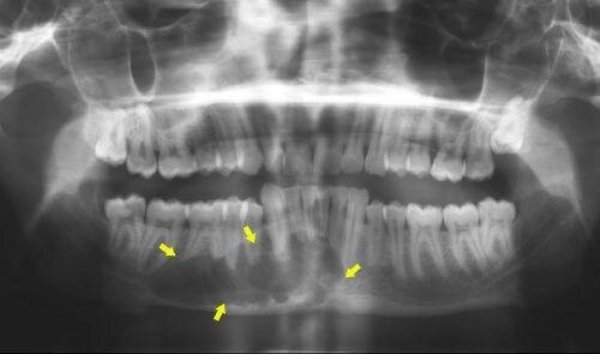

Рентгеновские снимки посттравматического остеомиелита челюсти: Медицинские случаи

Раздел: Образы вокруг